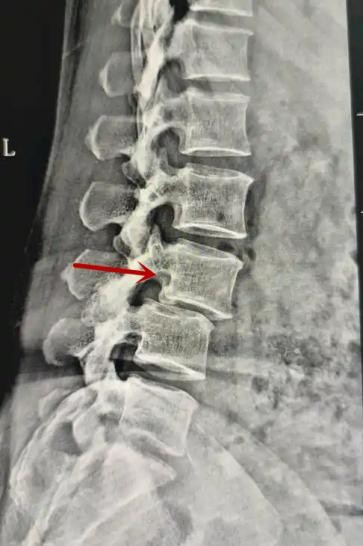

利器一:X線/DR

腰椎X線片作為最基礎(chǔ)的影像檢查手段,利于X線穿透人體組織后成像,以其快捷、直觀、價(jià)格低廉的特點(diǎn),X線檢查主要包括腰椎正側(cè)位、雙斜位以及過(guò)伸過(guò)屈位。主要用于觀察腰椎骨骼的情況,如椎體是否有骨折、骨質(zhì)增生程度、生理曲度的變化、椎體移位的情況等。然而,X線檢查也有它的局限性,無(wú)法判斷是骨折的新舊,對(duì)于椎體內(nèi)部結(jié)構(gòu)和周?chē)∪忭g帶組織(如脊髓神經(jīng)、椎間盤(pán)、韌帶等)的顯示不佳,另外X線作為有輻射檢查,孕婦及嬰幼兒謹(jǐn)慎選擇。

箭頭提示腰1椎骨折

箭頭提示腰3椎體滑脫